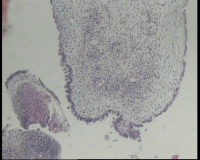

求会诊!左侧卵巢囊肿,够交界性浆液性囊腺瘤吗?

左侧卵巢囊肿大小约6.5x6.0厘米

碎囊壁组织5.0厘米一堆,壁厚0.1—0.4厘米,局灶囊壁见散在赘生物0.3,0.5厘米。另见完整小囊肿1.5x1.0厘米,无内容物,壁厚0.1厘米,内壁附0.8x0.7x0.4厘米赘生物,颗粒状

交界性浆液性乳头状囊腺瘤